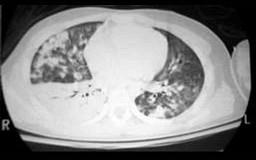

24岁,男,车祸后呼吸困难,CT检查如图,请选出最可能的诊断 ( )A、肺撕裂伤B、尘肺C、肺转移瘤D、肺挫伤E、肺结核

选项 A、肺撕裂伤 B、尘肺 C、肺转移瘤 D、肺挫伤 E、肺结核

答案 D